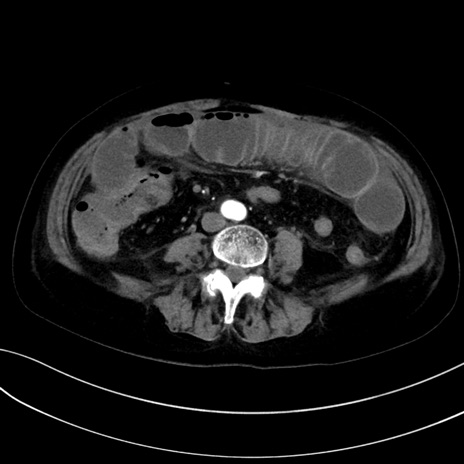

症例13 CT(横断像)1日半後